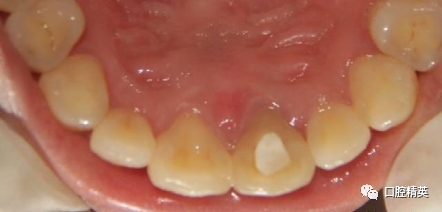

术前口内照

美学区软组织无退缩或外形改变。根尖区充填密实,根尖周组织初步愈合。记录牙体颜色变化。交代注意事项,4-6周复查。3-6个月完成美白及修复治疗。